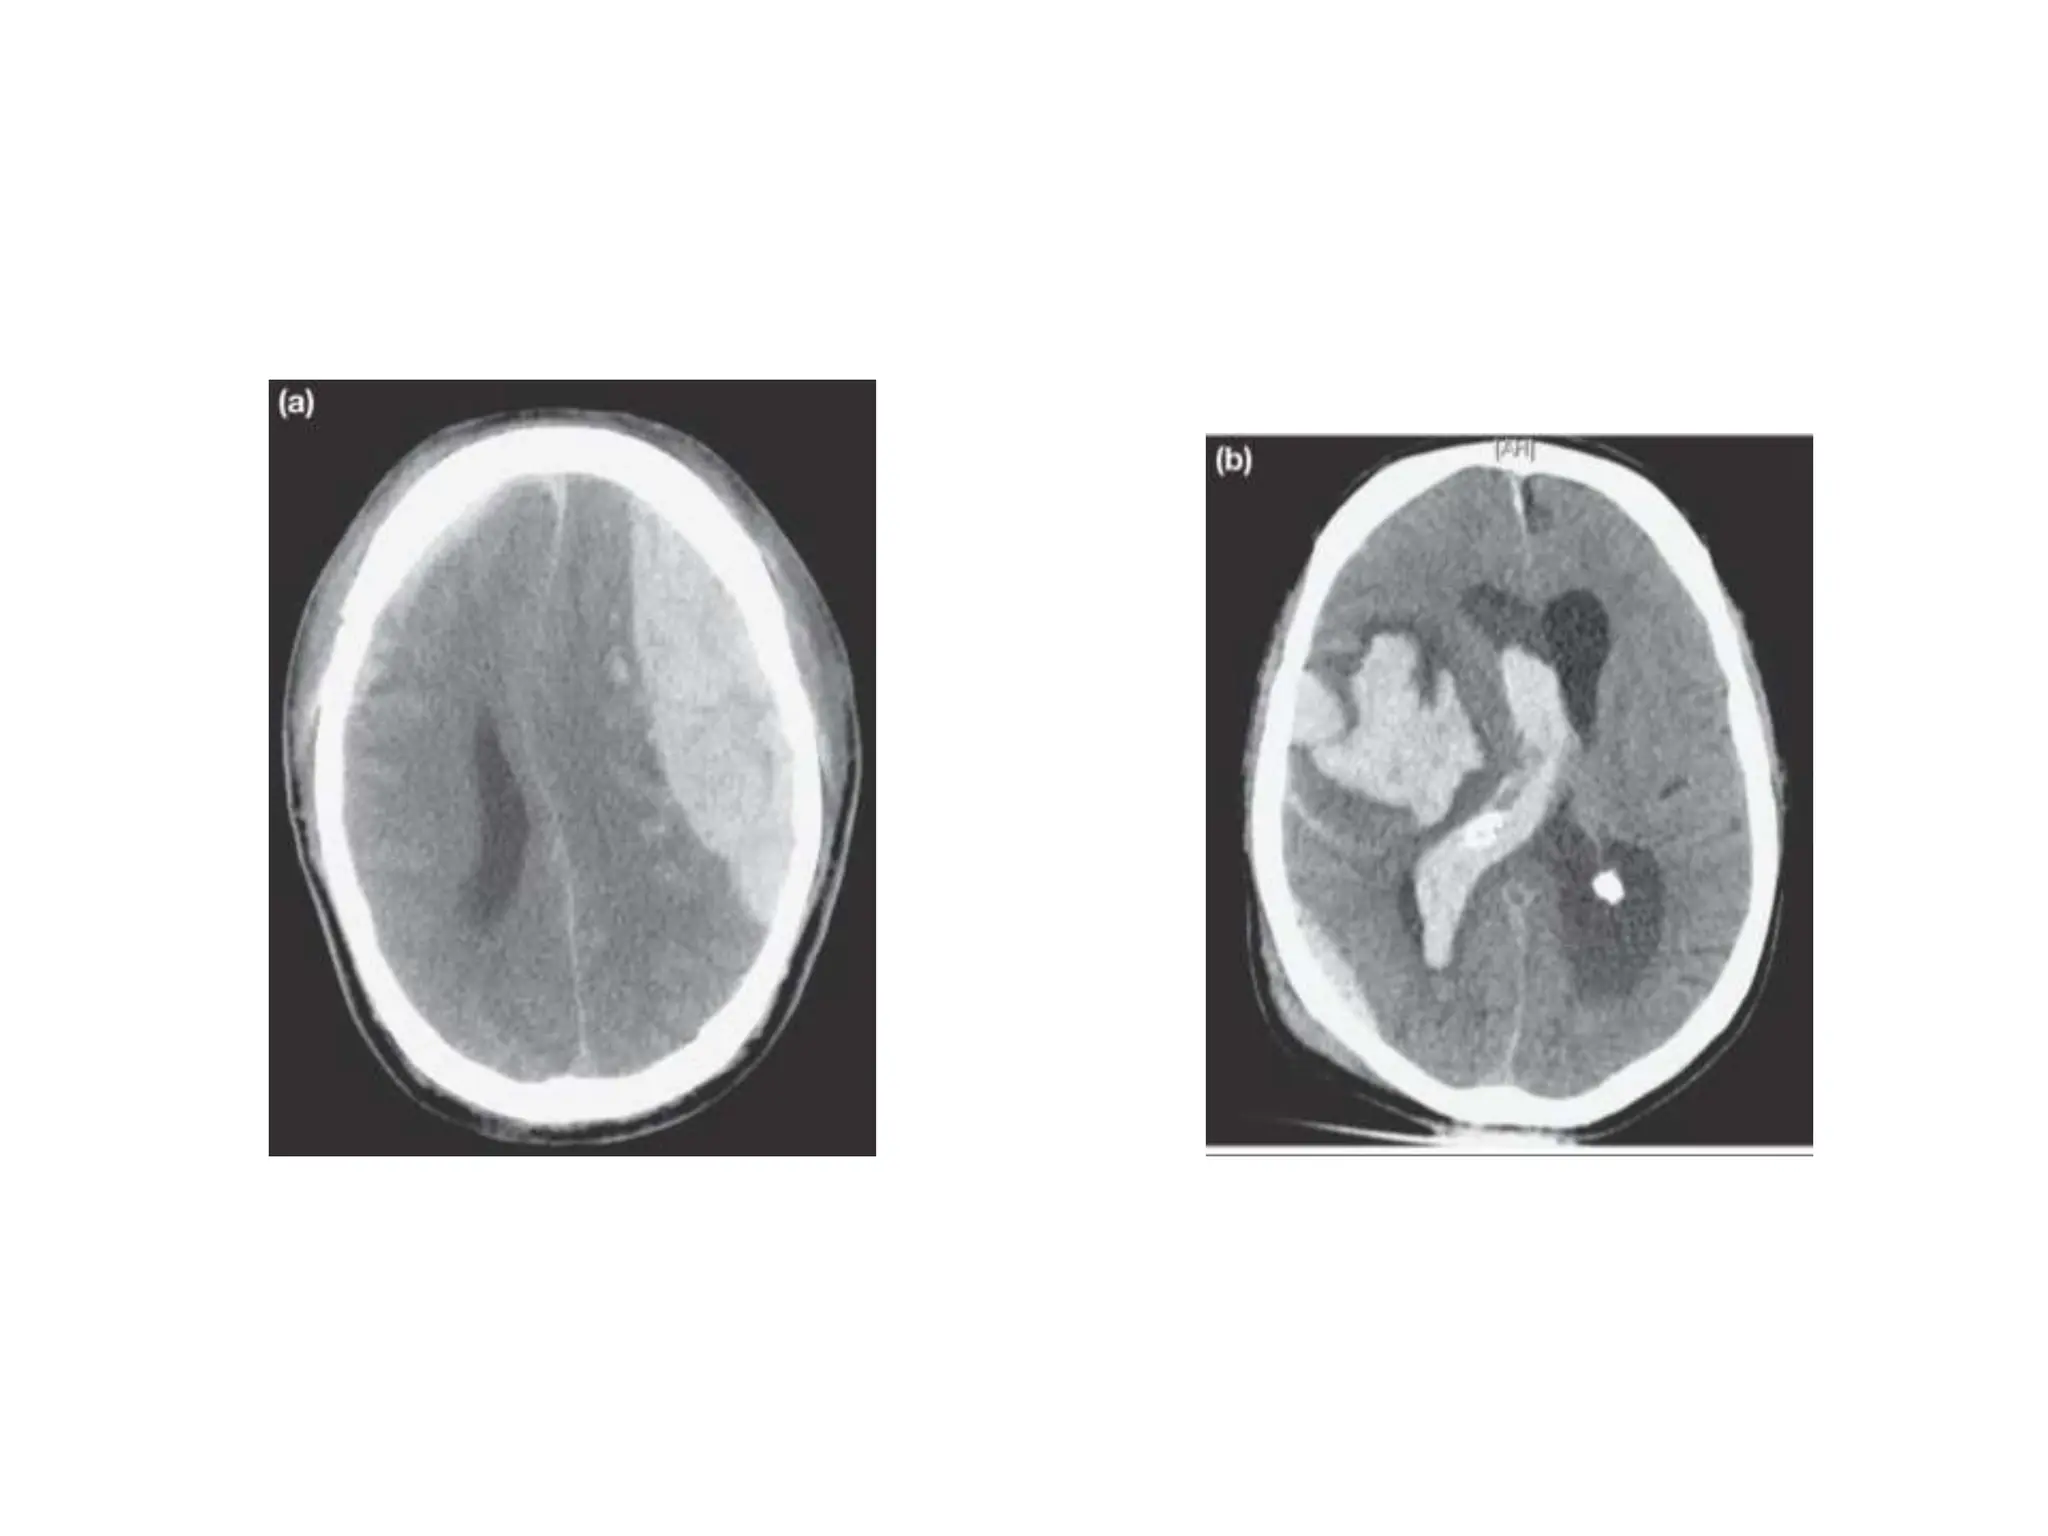

• Chronic subdural haematoma (Figure 28.7) is a

Chronic subdural haematoma •Chronic subdural haematoma (Figure 28.7) is a common • cause of acute neurological deterioration in older adults. • Cerebral atrophy in this age group results in stretching of the • cortical–dural bridging veins, which are then vulnerable to • rupture. The resulting haematoma can expand over days or • weeks by osmosis, ultimately producing symptoms of raised • ICP or focal defcits.

Acute subdural haematoma

• This is encountered in two broadly distinct

contexts. First, high-energy injury mechanisms can

results in an expanding haematoma with rapid

deterioration

Acute subdural haematoma •This is encountered in two broadly distinct contexts. First, high-energy injury mechanisms can result in the rupture of cortical surface vessels with signifcant associated primary brain injury. This results in an expanding haematoma with rapid deterioration